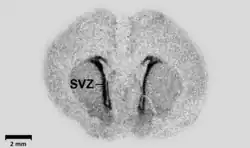

« Autoradiogramme » (ou « autoradiographie ») d'une coupe (coronale) de cerveau embryonnaire de rat. Le marquage radioactif a été fait avec des séquences oligonucléotidiques conjugués avec de l'35S-dATP (désoxyadénosine triphosphate) qui se lie à du GAD67, acide glutamique décarboxylase 67 radiomarqué. Cet acide se montre ici surexprimé dans deux zones situées dans l'espace sous-ventriculaire du cerveau (zones noires correspondant aux niveaux élevés de radioactivité qui ont marqué la pellicule).

La barre d'échelle noire (en bas à gauche de l’image) correspond à une longueur de mm. Elle est utilisée notamment pour observer le rôle de l'hypothalamus.